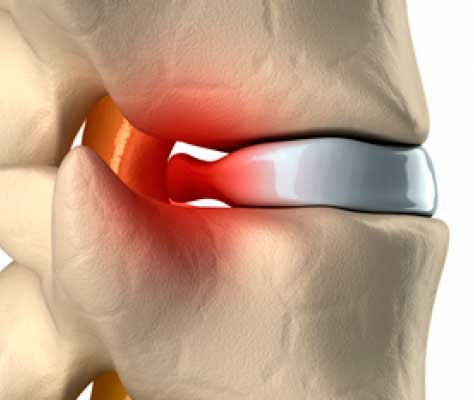

¿Las almohadas cervicales sirven para hernias discales?

Sí, las almohadas cervicales sirven para aliviar molestias derivadas de hernias discales cervicales, siempre que se usen correctamente ...